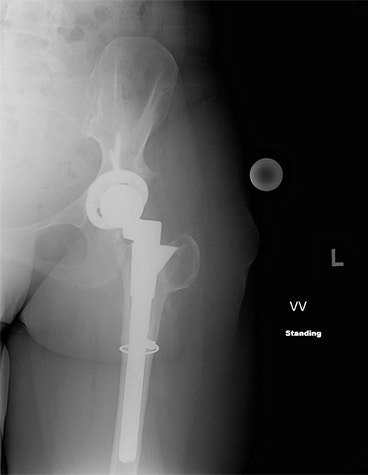

The surgeon planned a subtractive osteotomy in OrthoView to correct the leg length difference. The position and amount of the resection are identified in OrthoView, as can be seen in the templated image below.

A subtractive osteotomy was required to shorten the left leg by 20 mm — correcting the preoperative difference and compensating for any lengthening that might result from the THR.

For this patient, the DePuy S-ROM modular stem was chosen for its wide range of sizing options, including independent sizing of the sleeve and stem. In addition, the surgeon could confirm the correct amount of offset could be achieved within the S-ROM system.